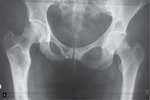

Konsultujący ortopeda zalecił dalszą diagnostykę w warunkach oddziału ortopedii, gdzie wykonano badania rentgenowskie i otwartą biopsję 1/3 bliższej prawej kości udowej. W badaniach RTG wykazano zmiany o mieszanym charakterze osteosklerotycznym i osteolitycznym, mogących odpowiadać dysplazji, w końcu bliższym prawej kości udowej, kręgu L3 kręgosłupa oraz I kości prawego śródstopia. Uwidoczniono asymetrię w wysokości ustawienia bioder, z pogrubieniem kości (ryc. 2).